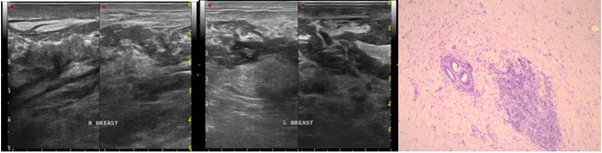

A 46-year-old female presented with warm and painful lumps in both breasts since 5 months before. There was history of unregulated DM for 6 years. Physical examination revealed edematous breasts with hyperemic skin.

There were no discrete mass detected on US, but it showed extended tissue distortion in all breast quadrants with skin thickening and wide edema. Lymph nodes enlargement also found on US, suggesting mastitis with differential diagnosis of inflammatory breast cancer. Core biopsy revealed no malignancy and consistent with features of DMP (Figure 3).

Figure 3 USG and histopathologic findings of a 46-year-old female presented with bilateral painful and warm breast lump turned out to be DMP.